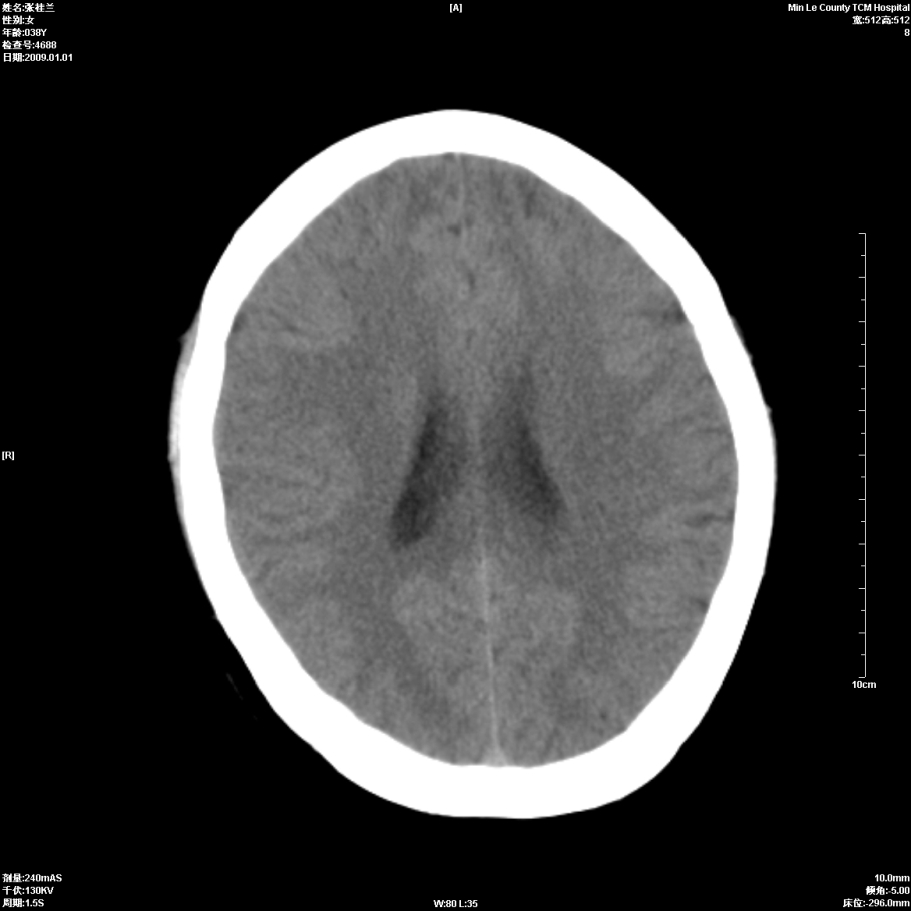

以下是引用hhcckk在2009-1-1 15:56:00的发言:[br]癫痫的原因一般与四种因素有关:[br] 1.遗传因素在一些有癫痫病史或有先天性中枢神经系统或心脏畸形的病人家族中容易出现癫痫;[br] 2.脑损害与脑损伤在胚胎发育中受到病毒感染放射线照射或其它原因引起的胚胎发育不良可以引起癫痫;胎儿生产过程中产伤也是引起癫痫的一个主要原因;颅脑外伤也可引起癫痫;[br] 3.颅脑其它疾病脑肿瘤脑血管病颅内感染等;[br] 4.环境因素;男性病人较女性病人稍多农村发病率高于城市另外发热精神刺激等也是癫痫发生的诱因。[br][br]此病例在额叶有片状低密度灶,无明显占位与负占位效应,结合癫痫的常见原因考虑[br]1、外伤后软化灶,包括产伤,可以结合病史鉴别[br]2、血管畸形的窃血现象形成的萎缩?

以下是引用xulianj在2009-1-1 16:09:00的发言:[br]支持:蛛网膜粒囊肿!